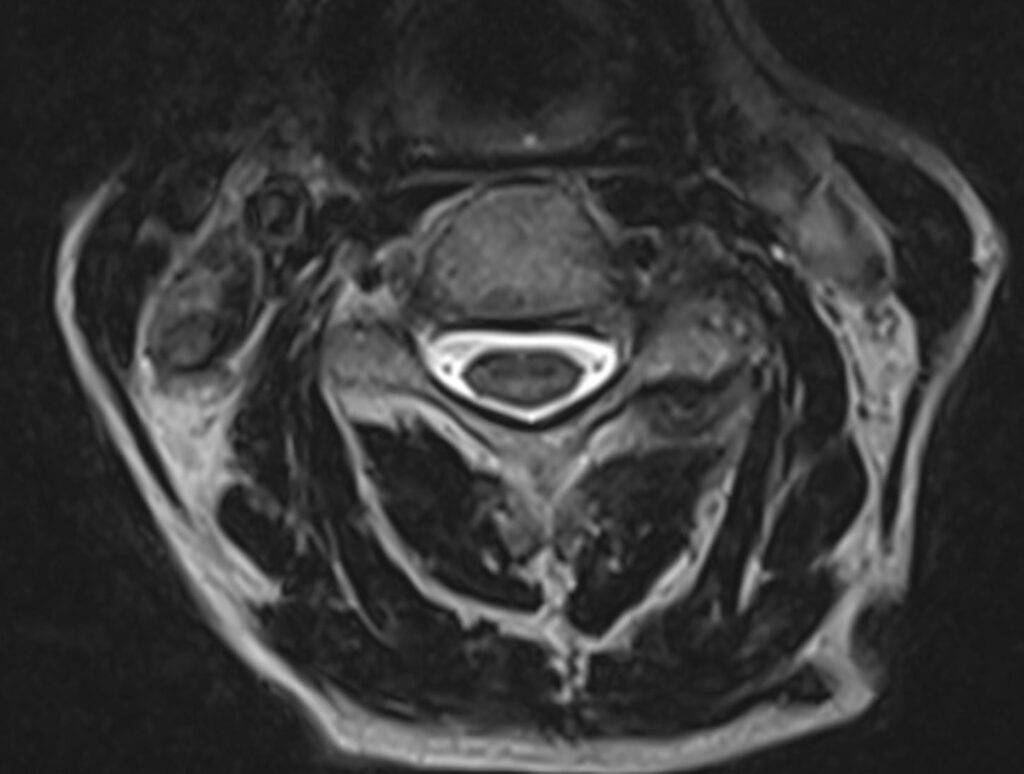

Die Magnetresonanztomographie der Halbwirbelsäule, kurz MRT HWS genannt, ist ein bildgebendes Diagnoseverfahren. In einer MRT HWS ist es möglich, den Bereich der Halswirbelsäule mit allen anatomischen Strukturen bildlich darzustellen. Besonders im Falle eines Verdachts auf Bandscheibenvorfall im Bereich der HWS ist eine Magnetresonanztomographie die bevorzugte Diagnosemethode.

Bei einer MRT der Halswirbelsäule wird der Nackenbereich abgebildet. Die unterschiedlichen anatomischen Strukturen können präzise dargestellt werden und dienen der Beurteilung von Erkrankungen der Halswirbelsäule.

Was sieht man alles auf einer MRT HWS?

| Wirbelkörper | Einzelne Wirbelkörper, Form und Struktur |

| Bandscheiben | Bandscheiben zwischen den Wirbeln |

| Rückenmark und Nervenwurzel | Gesamter Wirbelkanal |

| Weichteile | Muskeln, Bänder, Lymphknoten |